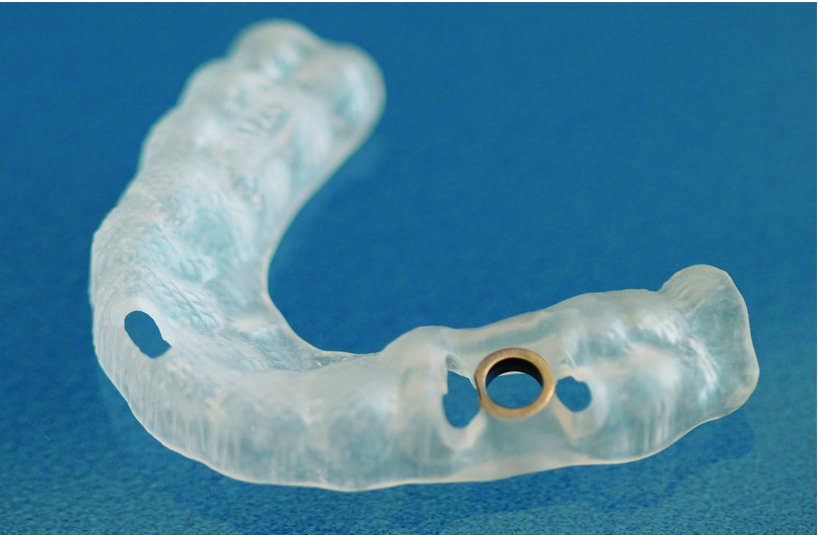

Herstellung der Bohrschablone

Durch die Schablone wird punktgenau der Knochen aufbereitet und das Implantat gesetzt.